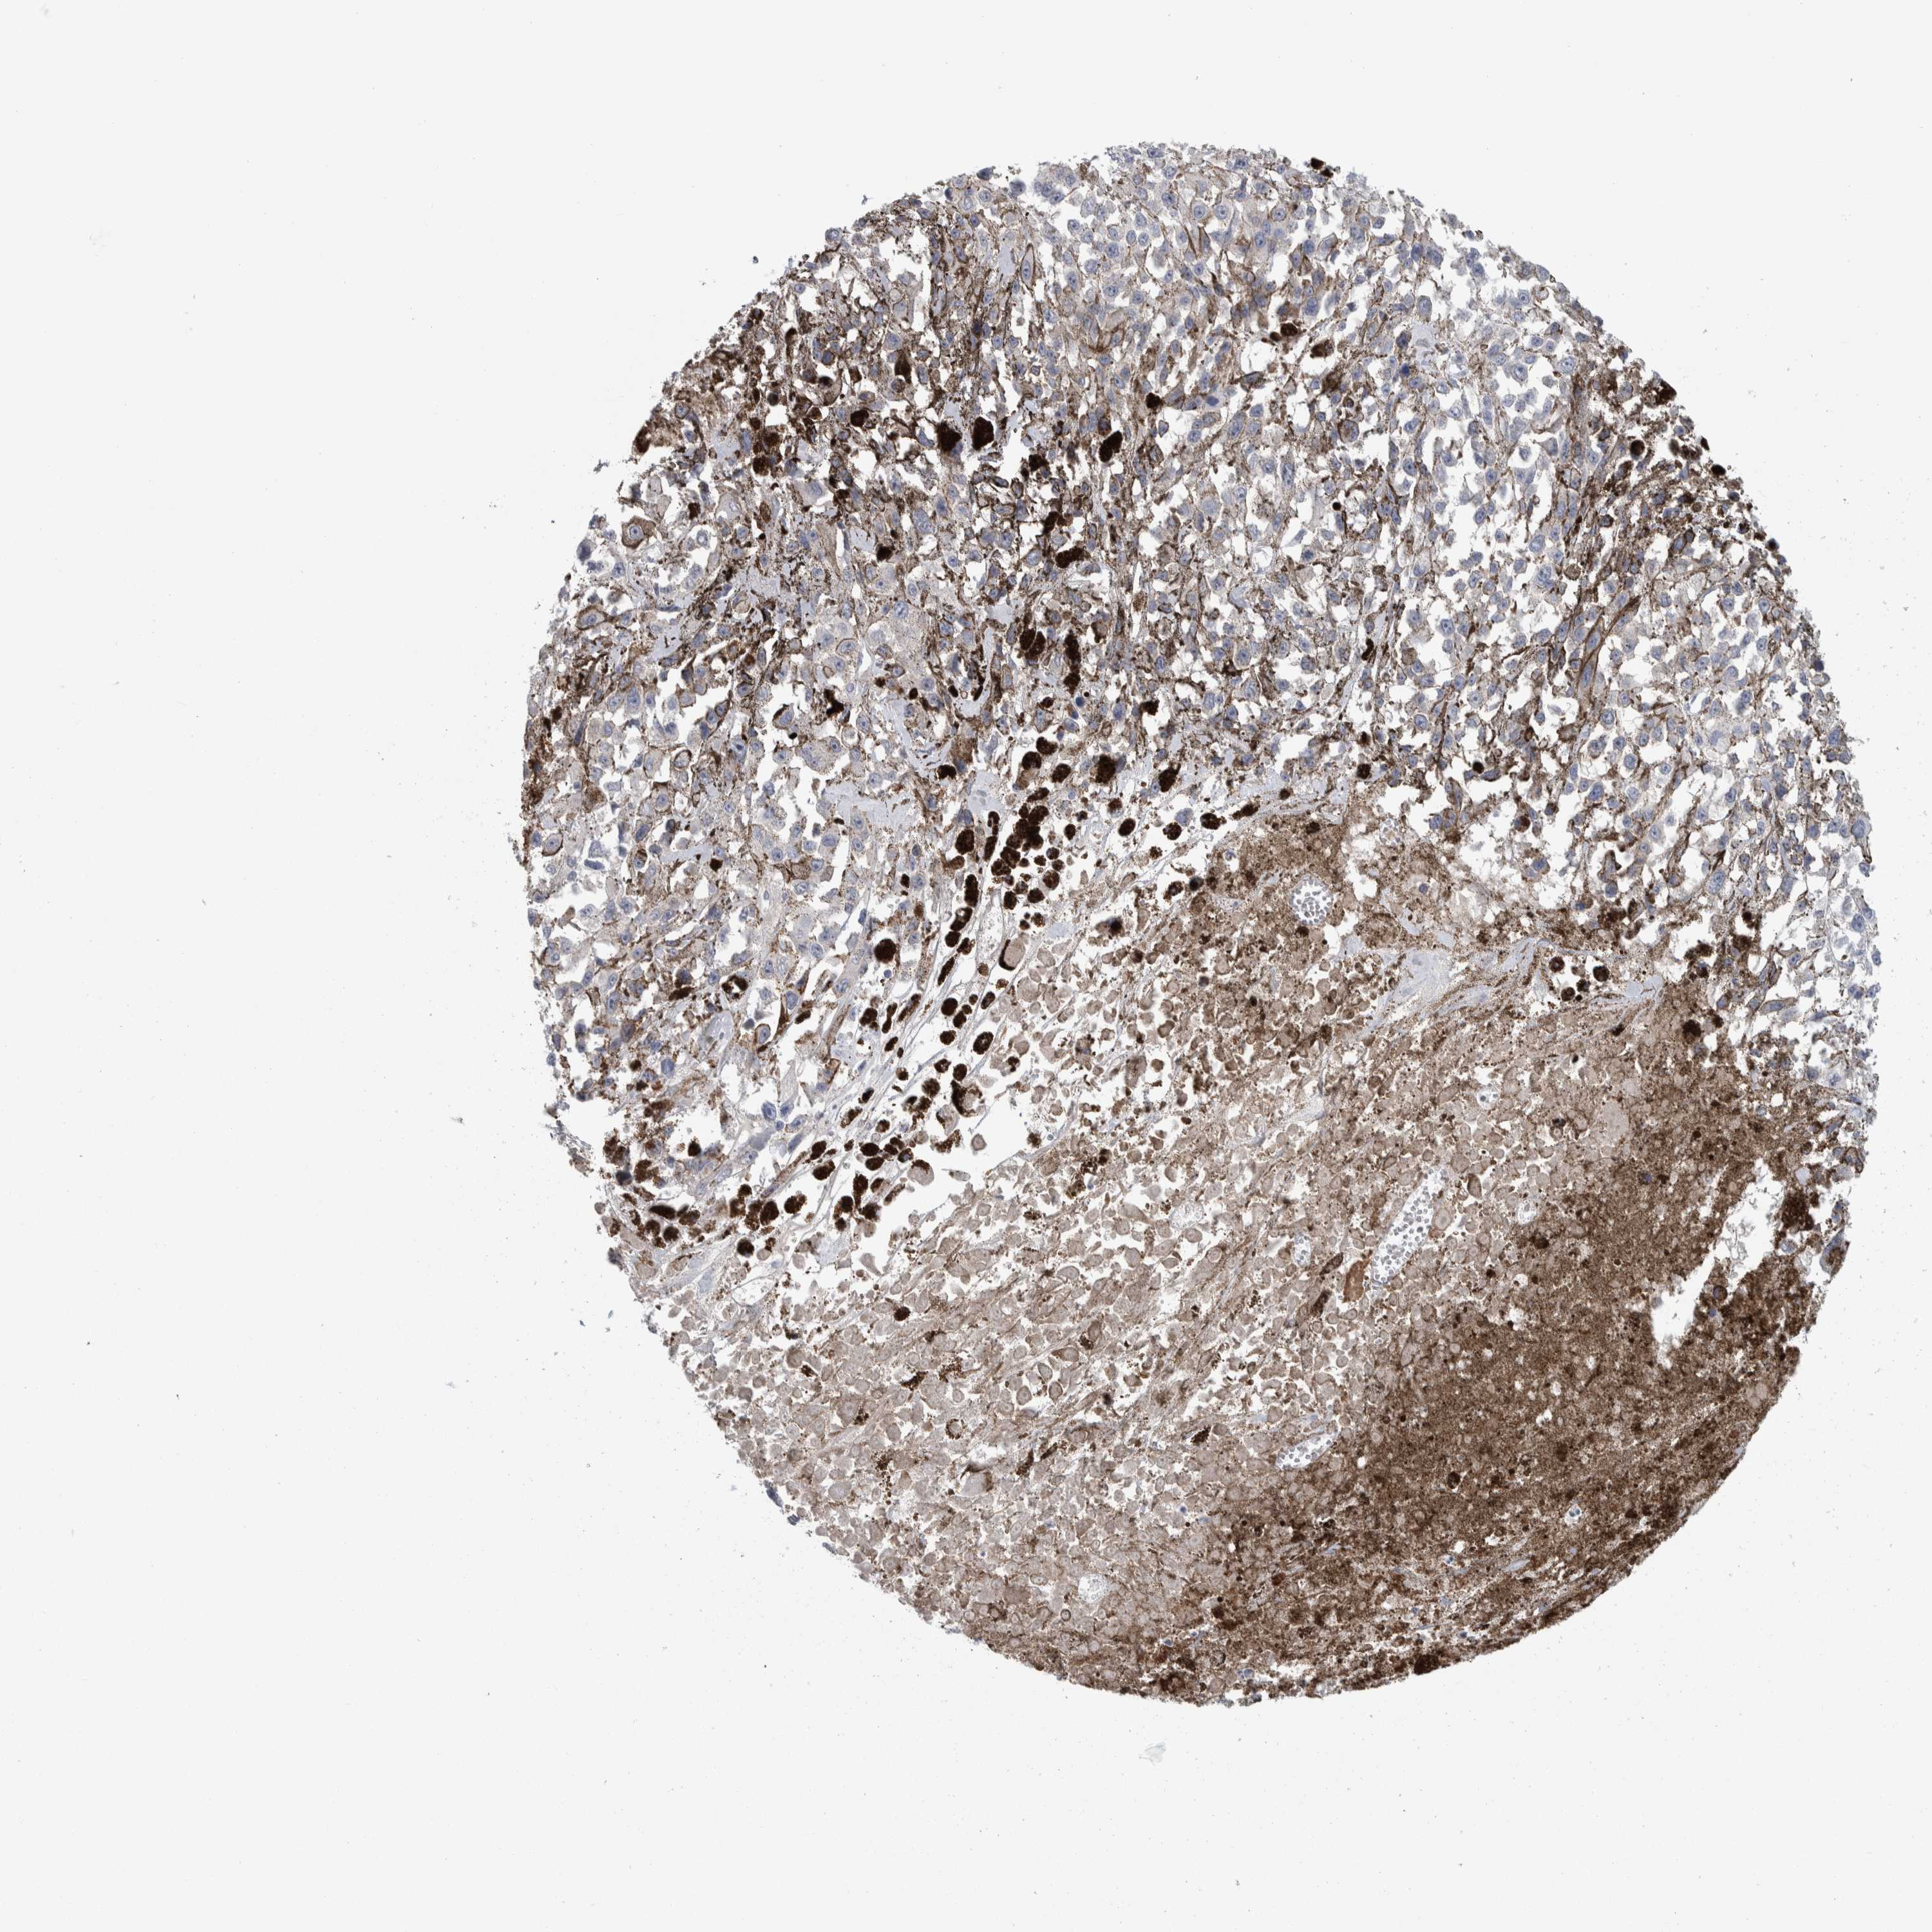

MELANOMA - Protein expressioni

A mouse-over function shows sample information and annotation data. Click on an image to view it in a full screen mode. Samples can be filtered based on level of antibody staining by selecting one or several of the following categories: high, medium, low and not detected. The assay and annotation is described here.

Note that samples used for immunohistochemistry by the Human Protein Atlas do not correspond to samples in the TCGA dataset.

Antibody stainingi

Antibody staining in the annotated cell types in the current human tissue is reported as not detected, low, medium, or high, based on conventional immunohistochemistry profiling in selected tissues. This score is based on the combination of the staining intensity and fraction of stained cells.

Each image is clickable and will lead to virtual microscopy that enables deeper exploration of all samples and also displays staining intensity scores, fraction scores and subcellular localization as well as patient and tissue information for each sample.

Antibody HPA023876

Staining

High

Medium

Low

Not detected

Intensity

Strong

Moderate

Weak

Negative

Quantity

>75%

75%-25%

<25%

None

Location

Nuclear

Cytoplasmic/membranous

Cytoplasmic/membranous,nuclear

Malignant melanoma, NOS

Malignant melanoma, Metastatic site